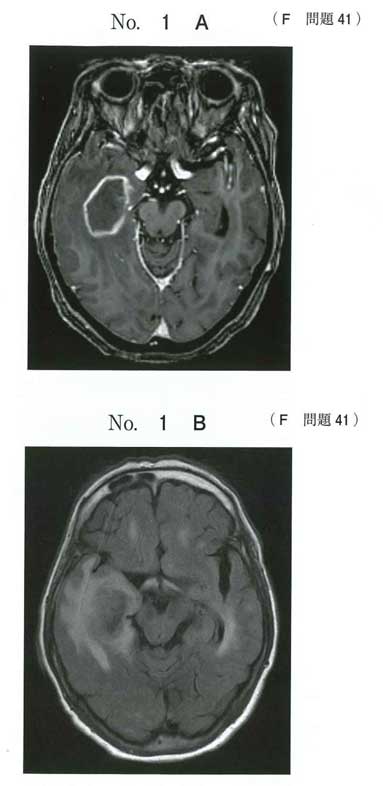

中枢神経原発悪性リンパ腫

画像はリンパ腫っぽくないけどね。病理とくに免疫染色が悪性リンパ腫なので。

c:悪性リンパ腫

中枢神経系原発悪性リンパ腫(PCNSL)は、脳や脊髄などの「中枢神経系」に発生する、B細胞由来の進行が速いリンパ腫です。高齢者に多く、頭痛、痙攣、片麻痺、認知機能障害などの局所症状が特徴。標準治療は大量メトトレキサート(MTX)療法などの化学療法で、放射線治療が併用されることもあります。

免疫抑制患者のPCNSLはリング状に染まることがあるので、画像としても一致する。ただ、国試に出すか?と思う。